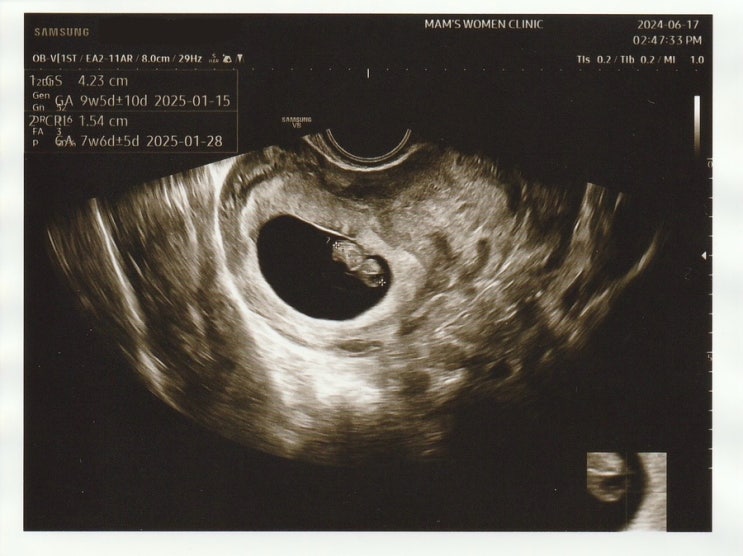

임신 9w5d / 입덧지옥 / 울산 맘스여성병원

지금까지 입덧약을 먹지 않고 잘 버텨왔기에 지난번 정기검진 때 입덧약을 처방받지 않았는데 9주에 들어서...